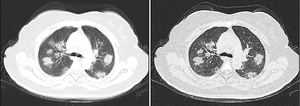

اقترحت الإرشادات التشخيصية الصادرة عن مستشفى تشونغنان بجامعة ووخان طرقًا للكشف عن العدوى بناءً على السمات السريرية والمخاطر الوبائية. تضمن هذا تحديد الأشخاص الذين لديهم على الأقل اثنين من الأعراض التالية بالإضافة إلى تاريخ من السفر إلى ووخان أو الاتصال بأشخاص آخرين مصابين: الحمى أوعلامات التصوير المقطعي للاتهاب الرئوي أو عدد خلايا الدم البيضاء الطبيعي أو المنخفض أو انخفاض عدد الخلايا الليمفاوية.[372] أظهرت دراسة نشرها فريق في مستشفى تونغجي في ووخان في 26 فبراير 2020 أن التصوير الطبقي المحوسب للصدر لـ COVID-19 لديه حساسية ونوعية أكثر (98٪) من تفاعل الپوليمريز المتسلسل (71٪).[373] قد تحدث نتائج سلبية كاذبة بسبب فشل مجموعة تفاعل الپوليمريز المتسلسل ، أو بسبب مشاكل في العينة أو مشاكل في إجراء الاختبار. من المرجح أن تكون النتائج الإيجابية الكاذبة نادرة..[374]